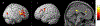

Results: The cancer group showed regional reductions over 12 months in frontal, temporal, and parietal gray matter on VBM, reduced FreeSurfer cortical thickness in prefrontal, parietal, and insular regions, and increased working memory-related fMRI activation in frontal, cingulate, and visual association cortex. Controls showed only reductions in fusiform gyrus on VBM and FreeSurfer temporal and parietal cortex thickness. Women with breast cancer showed higher estimated brain age and lower regional gray matter volume than controls at both time points. The cancer group showed a trend toward lower performance in attention, processing speed, and executive function at follow-up. There were no significant associations between brain imaging metrics and cognition or days on hormonal therapy.